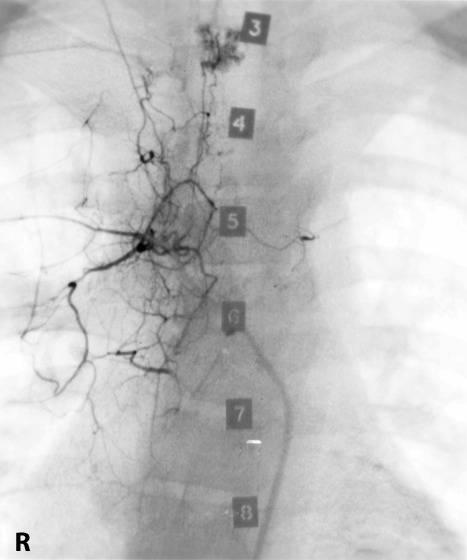

Post prandial mesenteric angina can be produced by strictures of the coeliac axis or superior mesenteric artery, usually both vessels are affected before symptoms occur. Here we see a stricture of the superior mesenteric artery which was successfully dilated and the patient was seen to eat breakfast with relish the next morning.